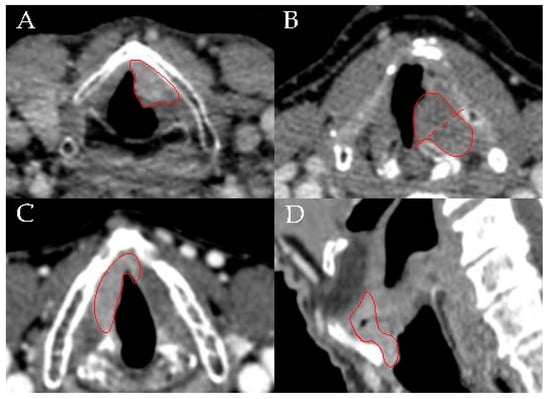

3.2. Radiological Characteristics

| Radiological characteristics (n = 46) | |||

| Tumor infiltration in VM | 0.077 | ||

| Superficial | 16 (34.8) | 92.9 | |

| Deep | 30 (65.2) | 68 | |

| Position relative to M-line | 0.875 | ||

| Anterior | 37 (82.2) | 76.6 | |

| Posterior | 1 (2.2) | 100 | |

| Both | 7 (15.6) | 71.4 | |

| Horizontal involvement AC | |||

| Yes | 13 (28.3) | 59.2 | 0.047 |

| No | 33 (71.7) | 83 | |

| Vertical involvement AC | <0.0001 | ||

| No | 32 (71.1) | 81.8 | |

| Supraglottic | 5 (11.1) | 100 | |

| Subglottic | 4 (8.9) | 75 | |

| Both | 4 (8.9) | 0 | |